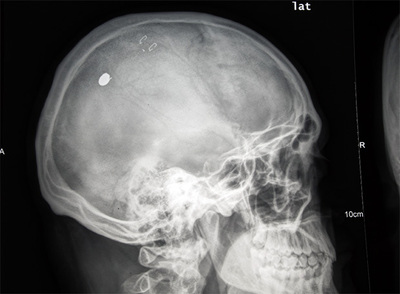

"Un silbido, un golpe seco, y dolor". Eso es lo que se siente al recibir un disparo en la cabeza, según M. P. D, un administrativo de 34 años residente en Puente de Vallecas. Ahora tendrá que convivir con un pequeño proyectil (posiblemente, un perdigón) pegado a su cráneo que los cirujanos, tras dos intentos, no han conseguido extraer. Alguien le disparó en la madrugada del pasado 18 de julio oculto en un edificio de la calle de Sierra Carbonera (Vallecas). Los disparos hirieron al menos a otras cuatro personas aquel día, según varios testigos. Sólo uno ha denunciado, según asegura el Cuerpo Nacional de Policía. Este fin de semana, el tirador, que aún no ha sido detenido, ha vuelto a actuar, afirman los vecinos. La policía desconoce este segundo episodio. Víctimas y vecinos se quejan de la falta de celo de los agentes para dar con el tirador. La policía lo niega.

Sobre las cuatro de la madrugada del día 18, al doblar la esquina de la calle de Monte Perdido con Sierra Carbonera, un proyectil de pequeñas dimensiones agujereó la parte superior izquierda de la cabeza de M. P. D. y se introdujo unos tres centímetros en su cuero cabelludo. Rápidamente sus amigos le atendieron. "Me salía muchísima sangre. Era muy escandaloso", relata. Lo siguiente que recuerda es que agentes de la Policía Municipal, la Nacional y el Samur acudieron al lugar. Pero todo ese despliegue no achicó al tirador. Mientras M. P. D. recibía las atenciones de los sanitarios, otro chico de 22 años acudió pidiendo ayuda. "Le habían pegado otro tiro en el cuello. También tenía el proyectil dentro", cuenta M.P.D.

"Me dijeron que ahora sacar el proyectil es más peligroso que dejarlo ahí dentro", explica M. P. D. De momento, el perdigón que le hirió se quedará incrustado en su cráneo. Sin que nadie haya conseguido apresar a quien lo disparó.